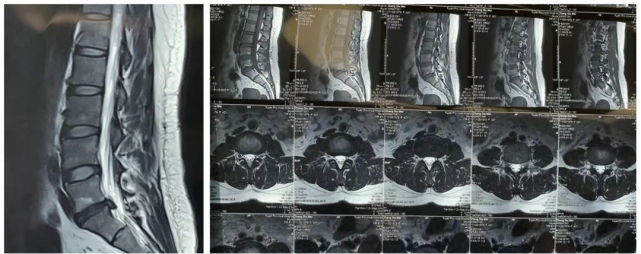

此次接受手术的是一名42岁的女性患者,腰椎间盘突出多年,之前一直保守治疗,近来疼痛加重,活动或体位变动时疼痛难忍,严重影响日常工作和行走能力,达到手术指症。术前,患者明确诊断为L5-S1节段腰椎间盘突出。

▲患者诊断为L5-S1节段腰椎间盘突出